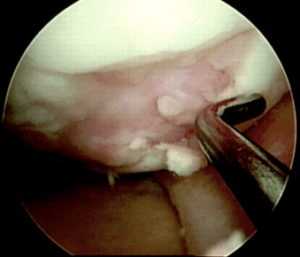

Далее осуществляется артроскопический доступ к мыщелку бедренной кости с поврежденным участком хряща. Производится очистка участка кюреткой и иссечение краев для получения ровного здорового контура. Затем вводится зонд с метками — с его помощью измеряют точный размер дефекта. Если дефект слишком большой или расположен очень далеко, операцию делают с помощью артротомии (открытым доступом).

Следующим этапом делают разрез тканей и получают доступ к тому участку кости, откуда будут брать трансплантат. Используется перекрестный принцип: если восстанавливают дефект на медиальном мыщелке, то трансплантат берут с боковой поверхности латерального и наоборот. Забор ткани осуществляется трубчатым долотом. Очень важно в момент “вбивания” долота сохранять точную перпендикулярность по отношению к поверхности хряща.

Количество забираемых цилиндрических костно-хрящевых фрагментов варьируется от трех до пяти и зависит от их размера: чем больше трансплантат, тем меньше их требуется. Обычно берут 3 трансплантата диаметром 10-11 мм или 5-6 диаметром 5-7 мм.

После получения необходимого количества костно-хрящевых фрагментов выполняется сверление первого “посадочного гнезда” на дефектном участке хряща. Осуществляется это также трубчатым долотом, но диаметр его на 1 мм меньше того, которое применялось для извлечения трансплантатов. Длина посадочного отверстия измеряется, под него подгоняется длина трансплантата, который осторожно фиксируется на предназначенное для него место способом press-fit. Процедуру повторяют необходимое количество раз. При этом отверстия сверлят таким образом, чтобы они были не параллельны и расходились веером от гипотетического центра кривизны мыщелка, это позволяет максимально точно восстановить кривизну суставной поверхности.